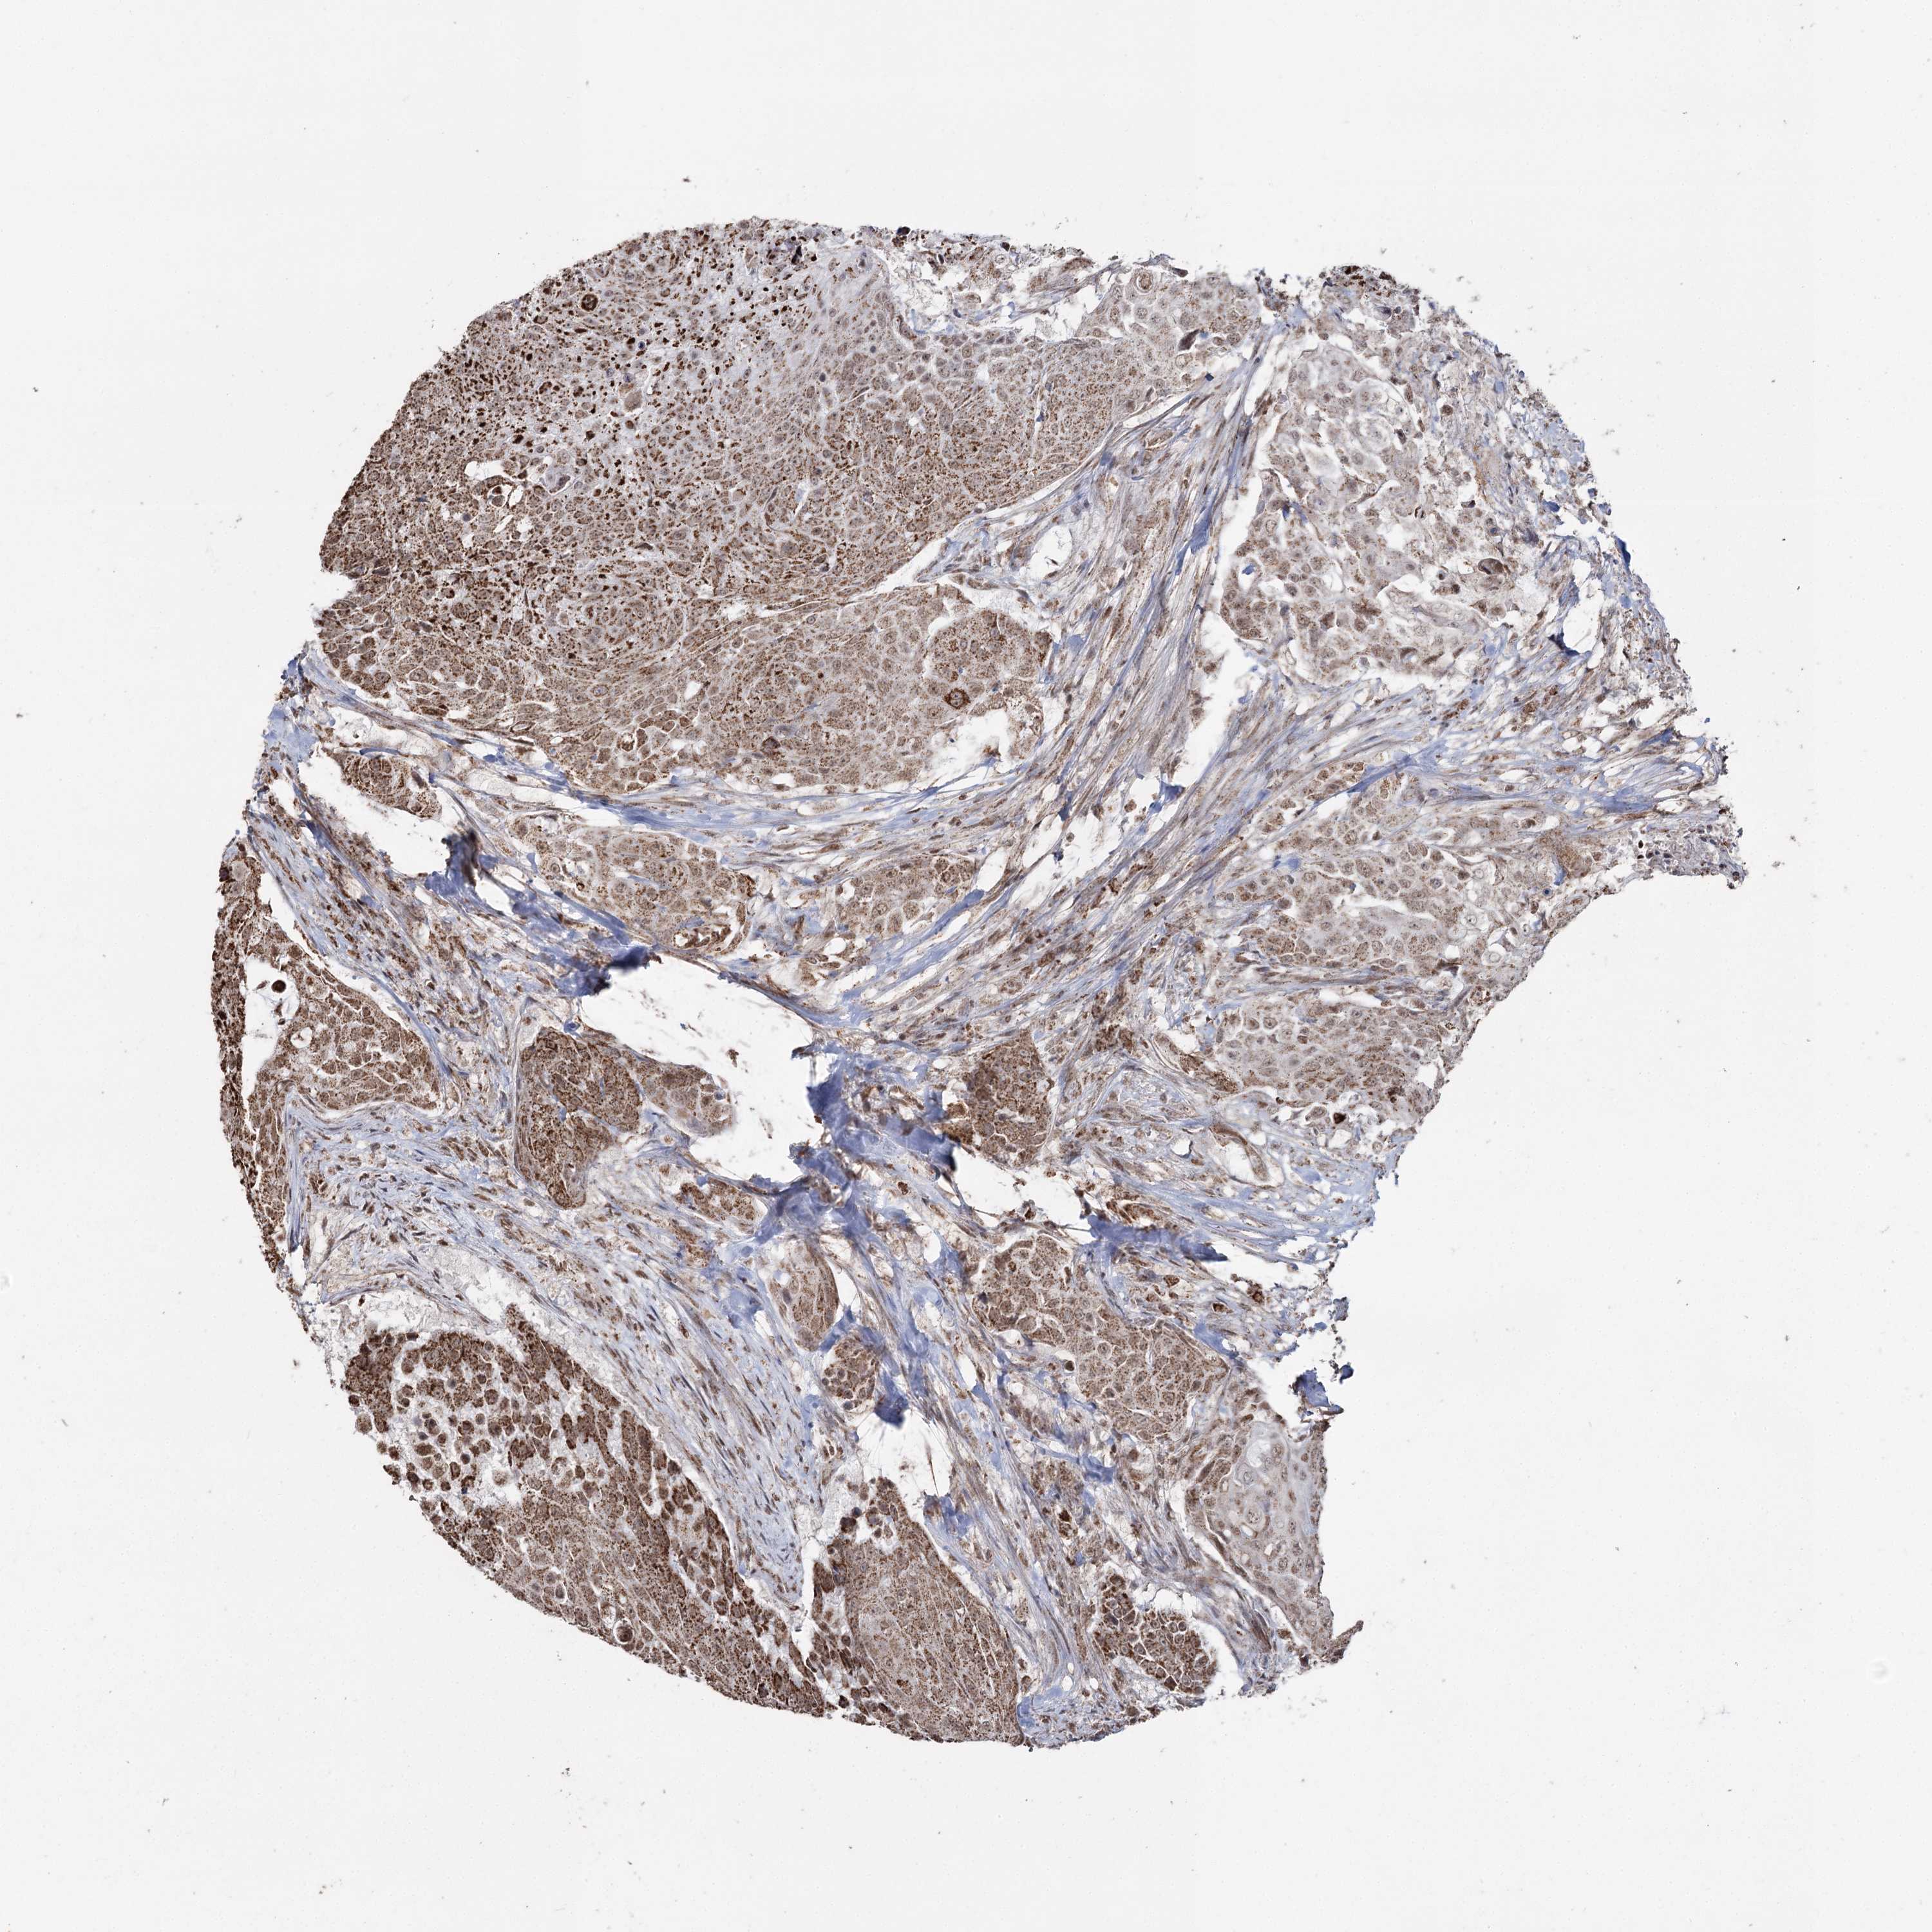

UROTHELIAL CANCER - Protein expressioni

A mouse-over function shows sample information and annotation data. Click on an image to view it in a full screen mode. Samples can be filtered based on level of antibody staining by selecting one or several of the following categories: high, medium, low and not detected. The assay and annotation is described here.

Note that samples used for immunohistochemistry by the Human Protein Atlas do not correspond to samples in the TCGA dataset.

Antibody stainingi

Antibody staining in the annotated cell types in the current human tissue is reported as not detected, low, medium, or high, based on conventional immunohistochemistry profiling in selected tissues. This score is based on the combination of the staining intensity and fraction of stained cells.

Each image is clickable and will lead to virtual microscopy that enables deeper exploration of all samples and also displays staining intensity scores, fraction scores and subcellular localization as well as patient and tissue information for each sample.

Antibody HPA038484

Antibody HPA038485

Staining

High

Medium

Low

Not detected

Intensity

Strong

Moderate

Weak

Negative

Quantity

>75%

75%-25%

<25%

None

Location

Nuclear

Cytoplasmic/membranous

Cytoplasmic/membranous,nuclear

Urothelial carcinoma, High grade

Urothelial carcinoma, Low grade

Urothelial carcinoma, NOS